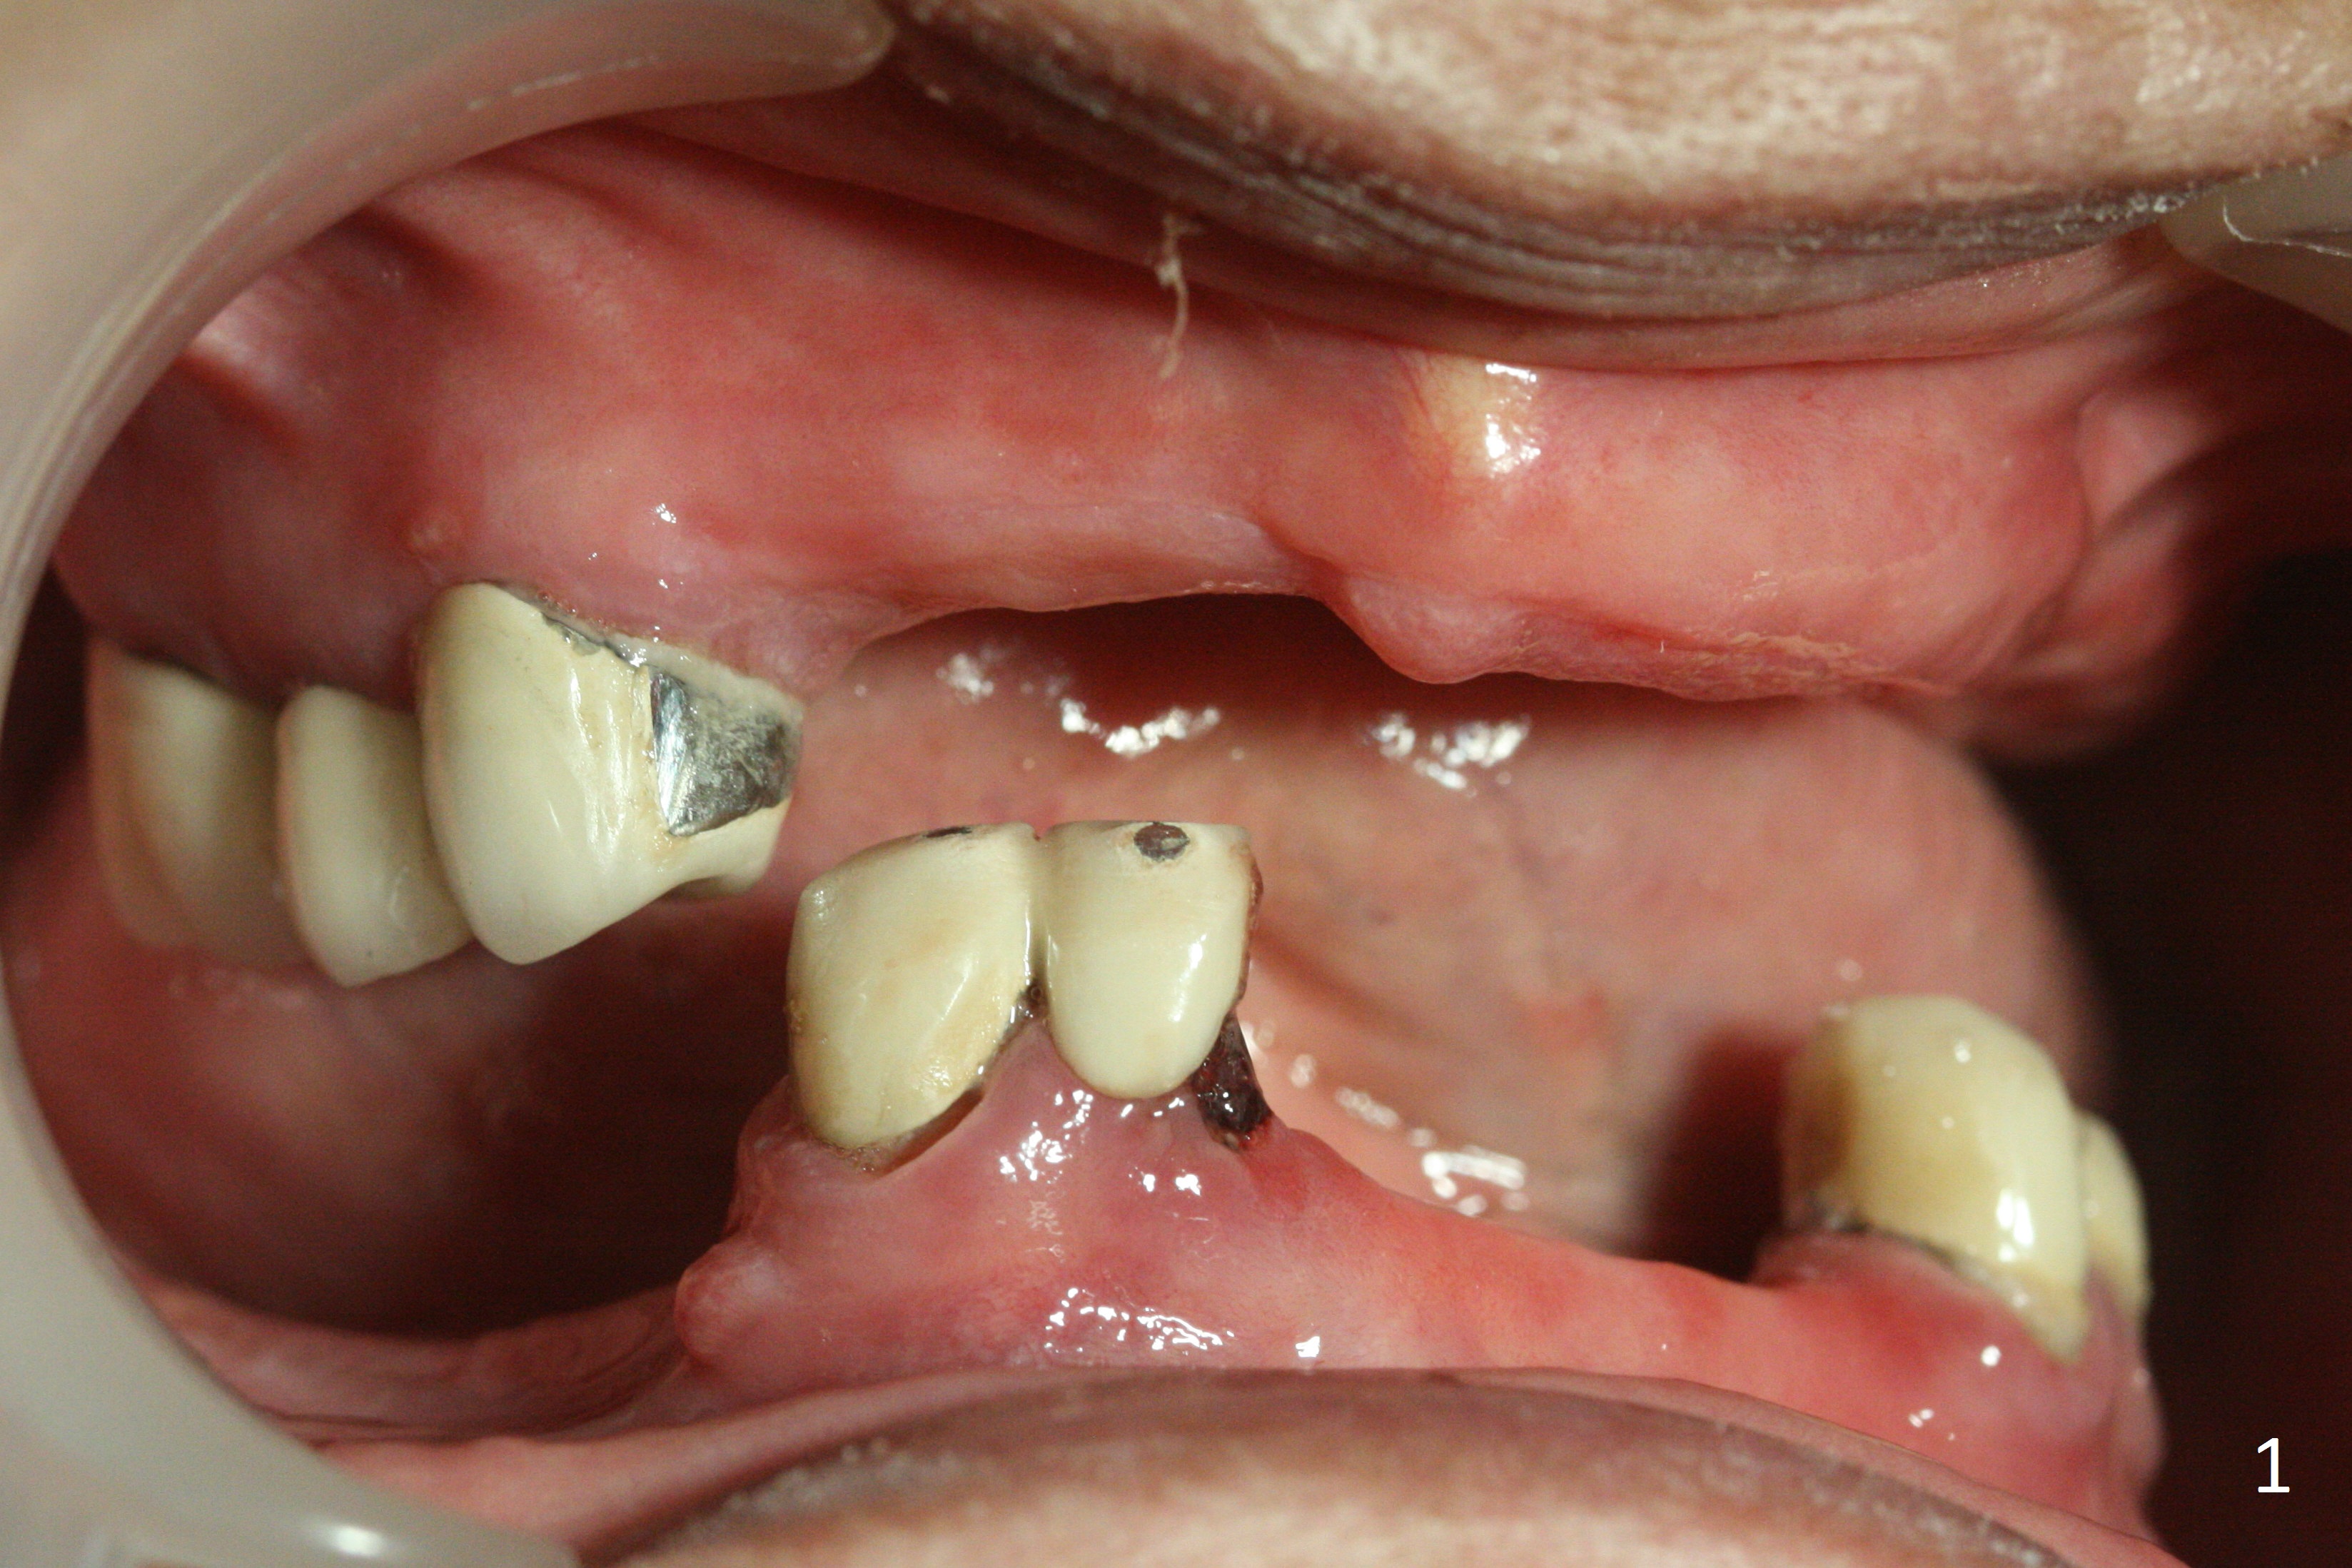

A 62-year-old woman has poor dentition (Fig.1). The most critical area is the upper left anterior: #9-11, which were extracted 4 months earlier (Fig.2). Implants will be placed at #9 and 11 with fabrication of a provisional bridge (Fig.3). After incision, use Magic Split to start bone expansion, followed by micro-osteotomes 1 and 1.5 mm and Magic Osteotomes 3 and 3.8 mm. If the transition between 1.5 and 3 mm osteotomes is not smooth, apply RT2. Place the smallest bone-level implants (for hybrid denture in the future) with gold coated abutments. There should be no interference with or without the partials and in and out. Next step should be removing splinted crowns at #26 and 27 (Fig.1), RCT for #27 and immediate implant at #26 (Fig.5,6 Metronidazole). In fact the splinted crowns at #26 and 27 were lost last week. The patient thinks that she needs 2 implants. The next one is to remove the crown at #5 for RCT (Fig.4).